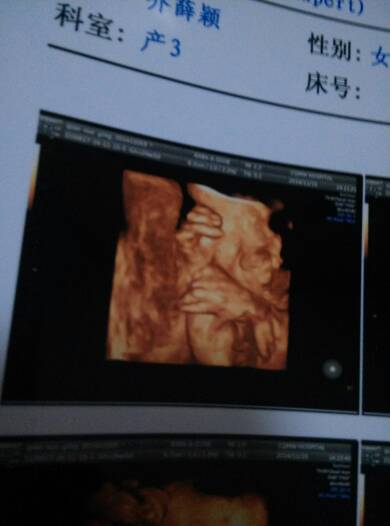

朋友说宝贝的手指母好长 宝妈和宝爸的手指母都很短 朋友说宝贝的手指母好长。宝妈和宝爸的手指母都很短。 点击展开 彤彤滴妈咪 2014-12-25 20:38 为您推荐: 其他回答 你好这些情况生下来再看,如果是小宝宝四肢都特别长的话,你还是需要注意一下 最优秀医生 2014-12-26 02:13 现在还看不出来 琳子💄 2014-12-26 01:04 好可爱!! 祝好人一身平安 2014-12-25 21:47 嗯嗯,好的 傻 丫 头 2014-12-25 21:15 噢噢,估计上海的医院会贵些 傻 丫 头 2014-12-25 21:14 加载更多 相关问题 有宝妈长副乳的吗?从怀孩子开始随着胸部长大,腋下也长了一个小疙瘩,现在生了孩子有大手指母那么大,不 宝妈们知道宝宝为什么那么爱吃手指,都不怎么爱喝奶了 有宝妈怀孕手指容易麻的吗,特别是睡觉的时候特别麻,知道为啥吗